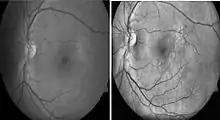

Diabetic retinopathy

Diabetic retinopathy is a disease of the retina that is diagnosed predominantly by fundoscopic images. Diabetic patients in industrialised countries generally undergo regular screening for the condition. Imaging is used to recognize early signs of abnormal retinal blood vessels. Manual analysis of these images can be time-consuming and unreliable.[74][75] CAD has been employed to enhance the accuracy, sensitivity, and specificity of automated detection method. The use of some CAD systems to replace human graders can be safe and cost effective.[75]